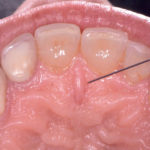

Gestione dinamica e analisi estetica dei trattamenti di denti vitali nel settore anteriore: anestesia...

Afronte del continuo sviluppo di nuovi sistemi adesivi, nonché di nuovi materiali compositi e ceramici in odontoiatria, la gamma di indicazioni cliniche per tutti...